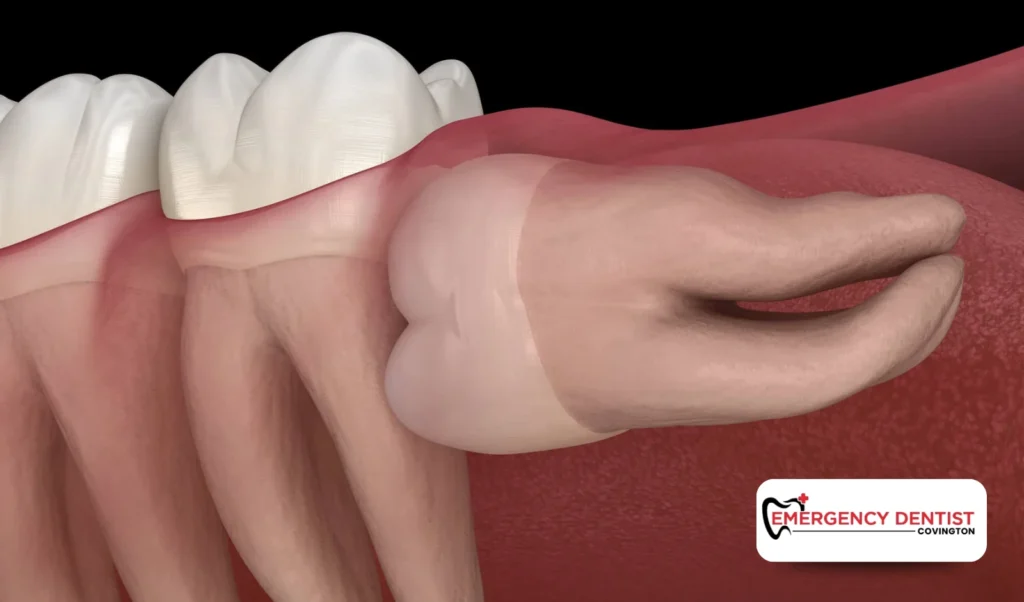

What Is Impacted Wisdom Tooth Removal?

An impacted wisdom tooth is one that cannot fully break through the gums. Some are partly visible, while others remain completely beneath the surface.

Impacted wisdom tooth removal is slightly more involved than a simple teeth extraction. Because the tooth may be beneath gum tissue or partially covered by bone, oral surgery is required. The goal is to carefully remove the tooth while protecting surrounding tissue.

- Impacted wisdom teeth trapped beneath gum tissue

- Teeth growing sideways toward nearby molars

- Fluid filled sacs forming around an impacted wisdom tooth

When left untreated, impacted wisdom teeth can contribute to infection, gum disease, and even bone damage. Removing wisdom teeth early often prevents more serious issues later.